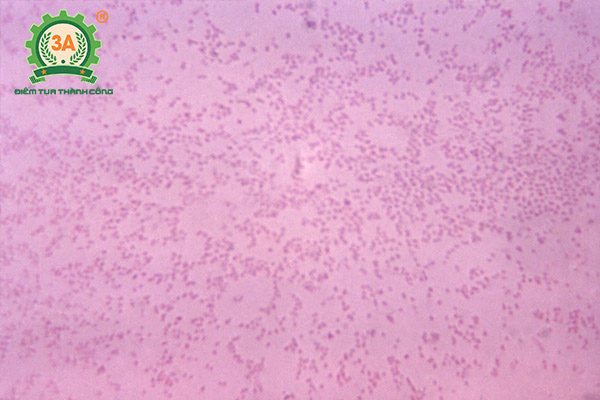

Vi khuẩn Pasteurella Multocida là nguyên nhân gây ra bệnh tụ huyết trùng trâu bò. Vi khuẩn tấn công vào cơ thể vật chủ làm xuất hiện các tụ và xuất huyết tại những vùng nhạy cảm trên cơ thể. Bệnh tiến triển nặng hơn, vi khuẩn đi sâu vào máu gây ra nhiễm trùng máu. Trâu bò khi mắc bệnh nặng còn được gọi là bại xuất huyết trâu bò.

Đặc điểm của vi khuẩn tụ huyết trùng